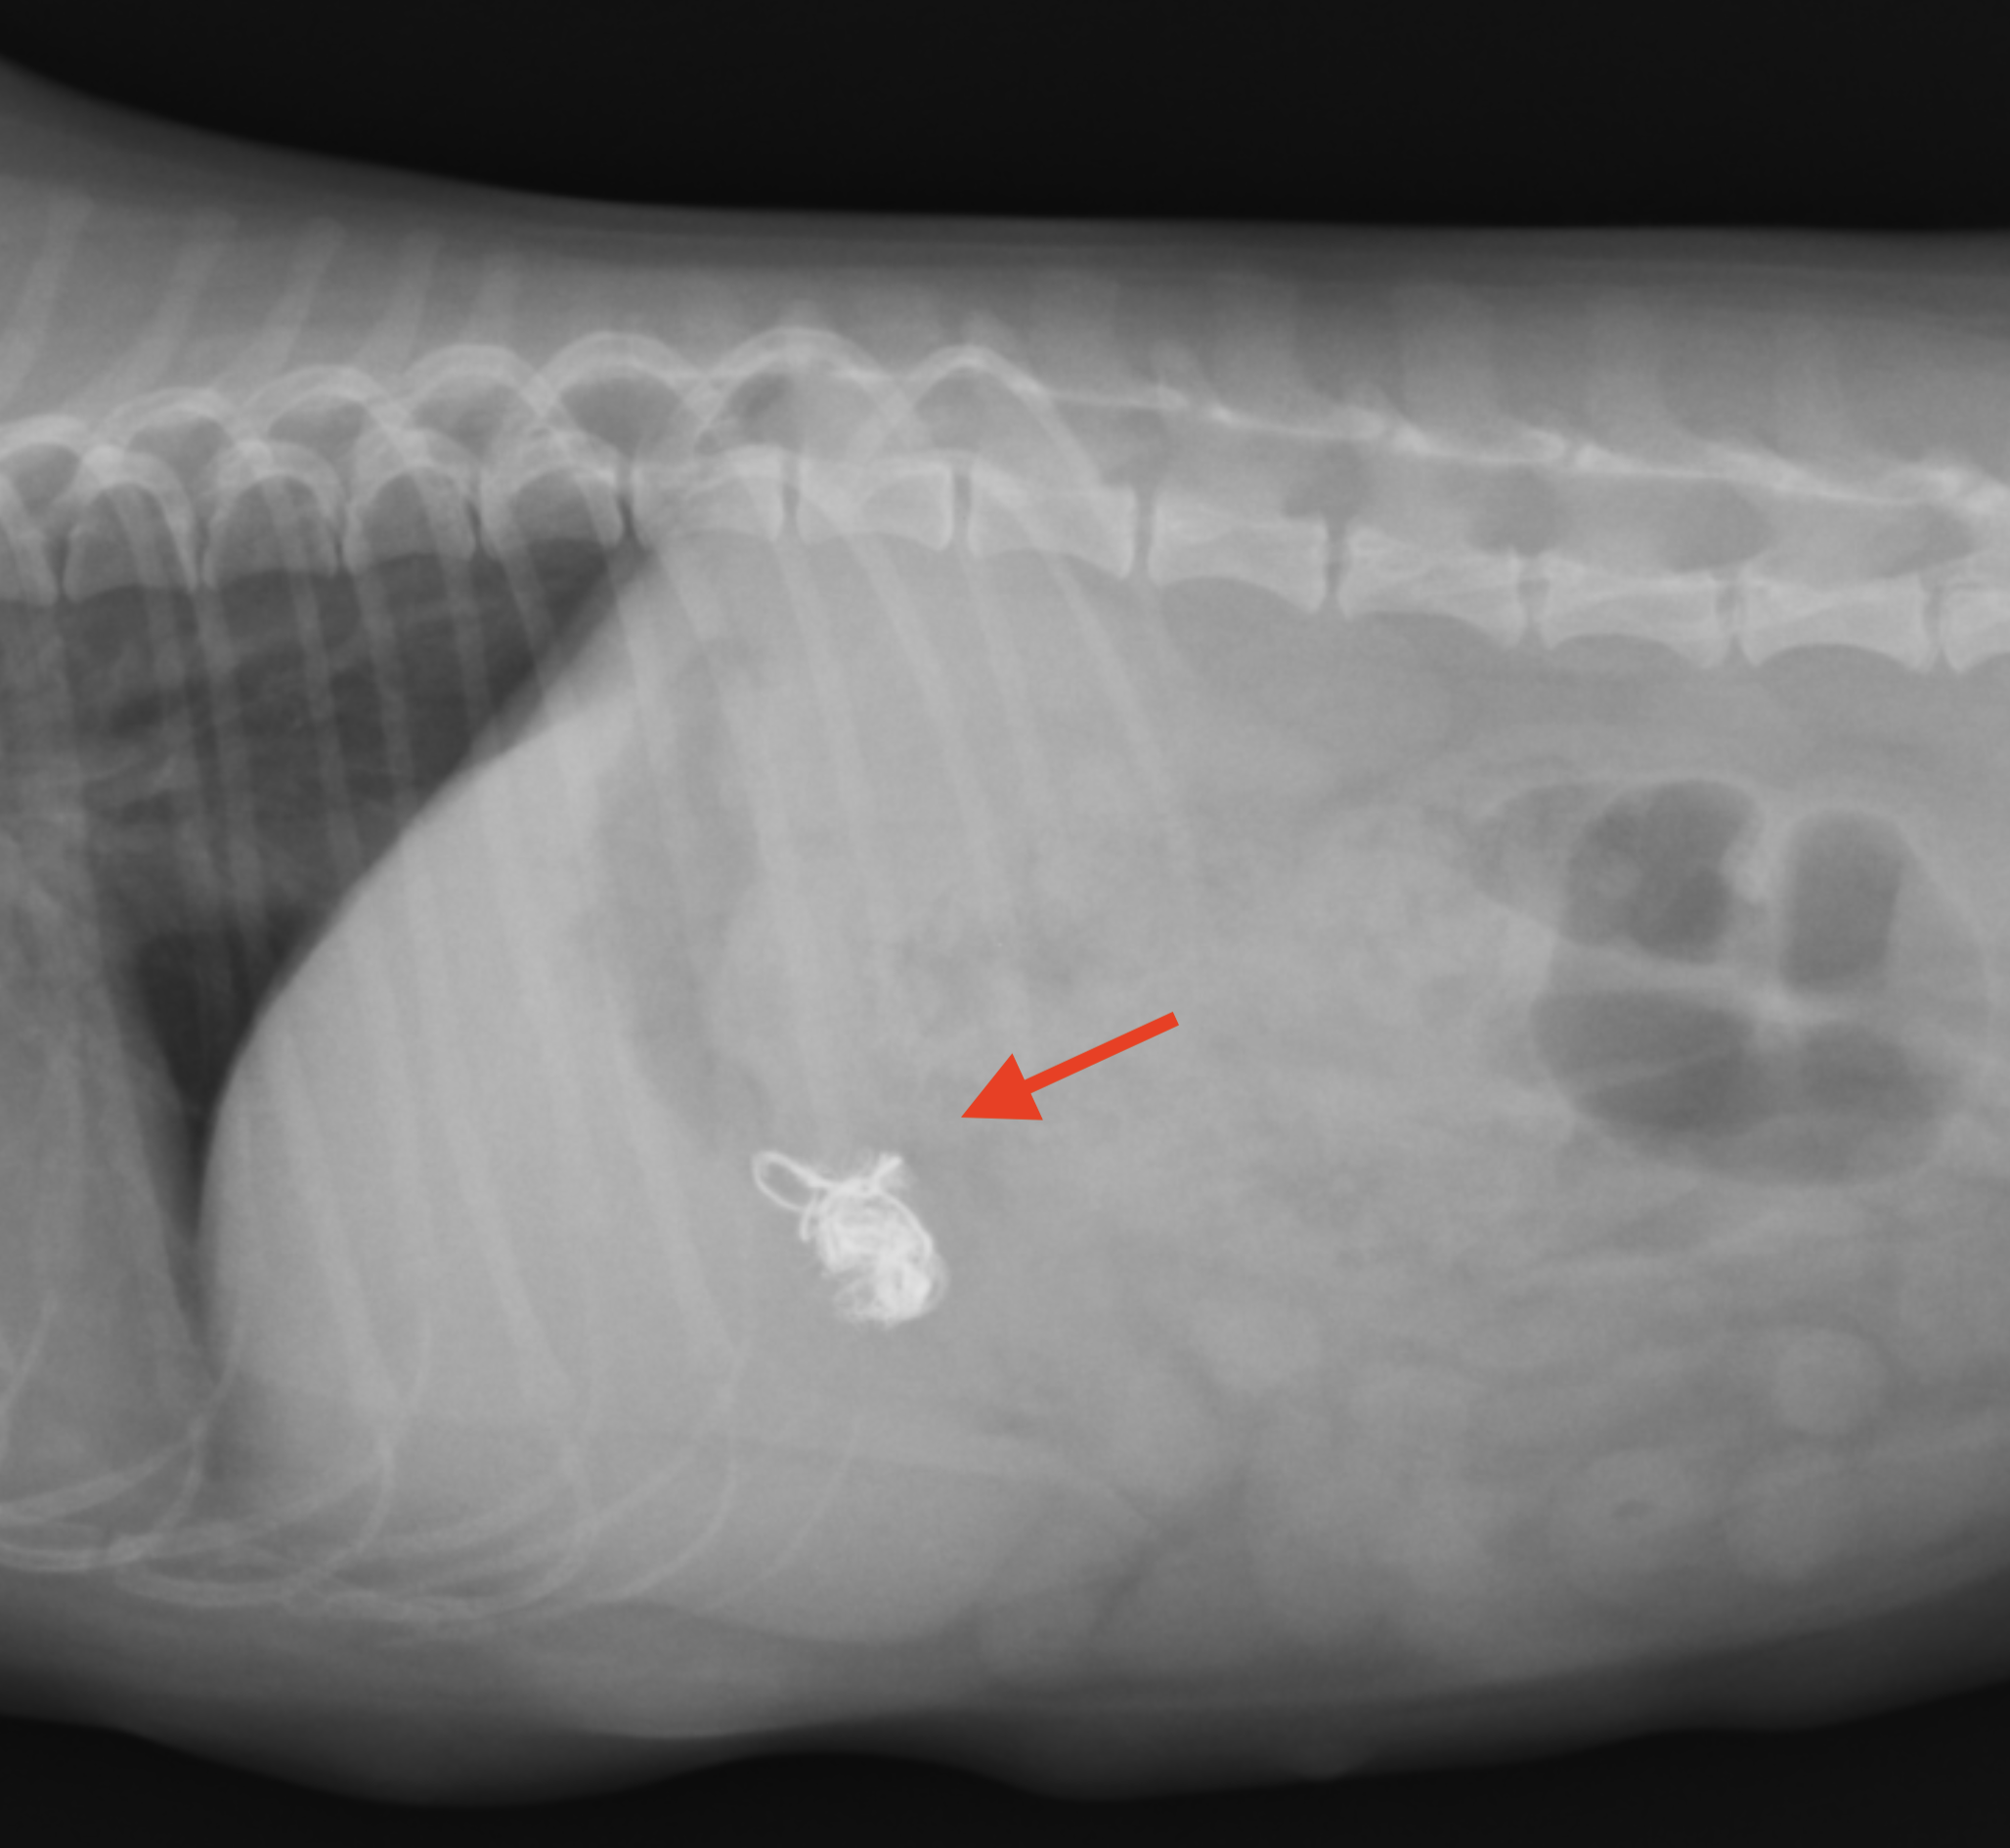

Mix犬 1歳 雌

頻回の嘔吐を主訴に来院しました。元気食欲には問題がなく、触診や聴診でも異常は認めませんでした。腹部レントゲン検査にて胃内にX線不透過性の異物を認めたため、誤食による胃内異物と診断されました。すでに嘔吐しているものの異物が吐けていなかったことから、催吐処置はせずに内視鏡で摘出することになりました。その日のうちに内視鏡を行うことになり、胃からは電源コードが摘出されました。 摘出後からは症状もなくなり、無事に退院することになりました。

レントゲン検査で確認された白いコード状の異物(赤矢印)